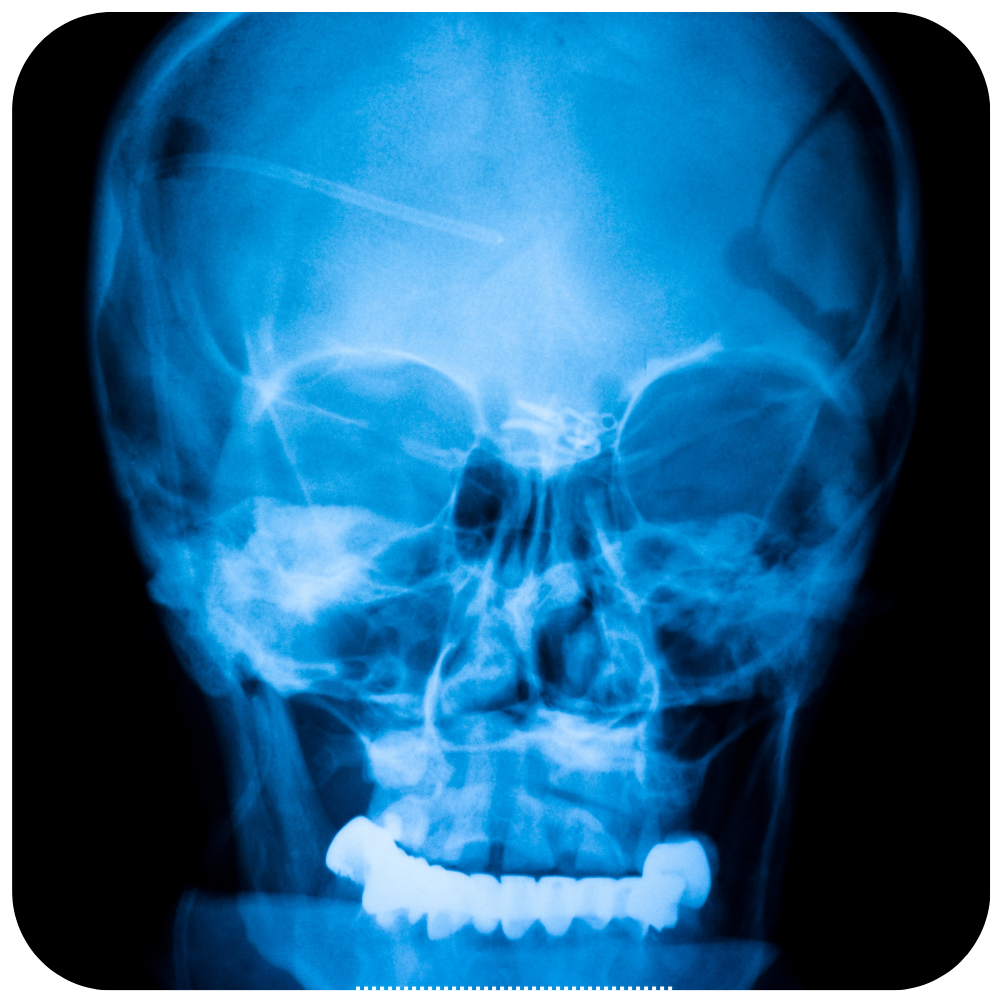

Craneotomía Operación en la que se extrae un pedazo del cráneo. Una craneotomía se realiza para que los médicos puedan extraer un tumor o tejido anormal del cerebro. También se puede realizar para extraer sangre o coágulos del cerebro, aliviar la presión en el cerebro después de una lesión o…